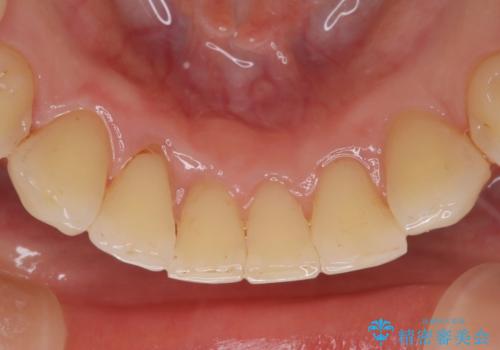

エアフローだけで歯が白くなったと喜んでいらっしゃいました。新しいマウスピースが届くまでの間はホームホワイトニングを行い歯の内部から白くしていきます。